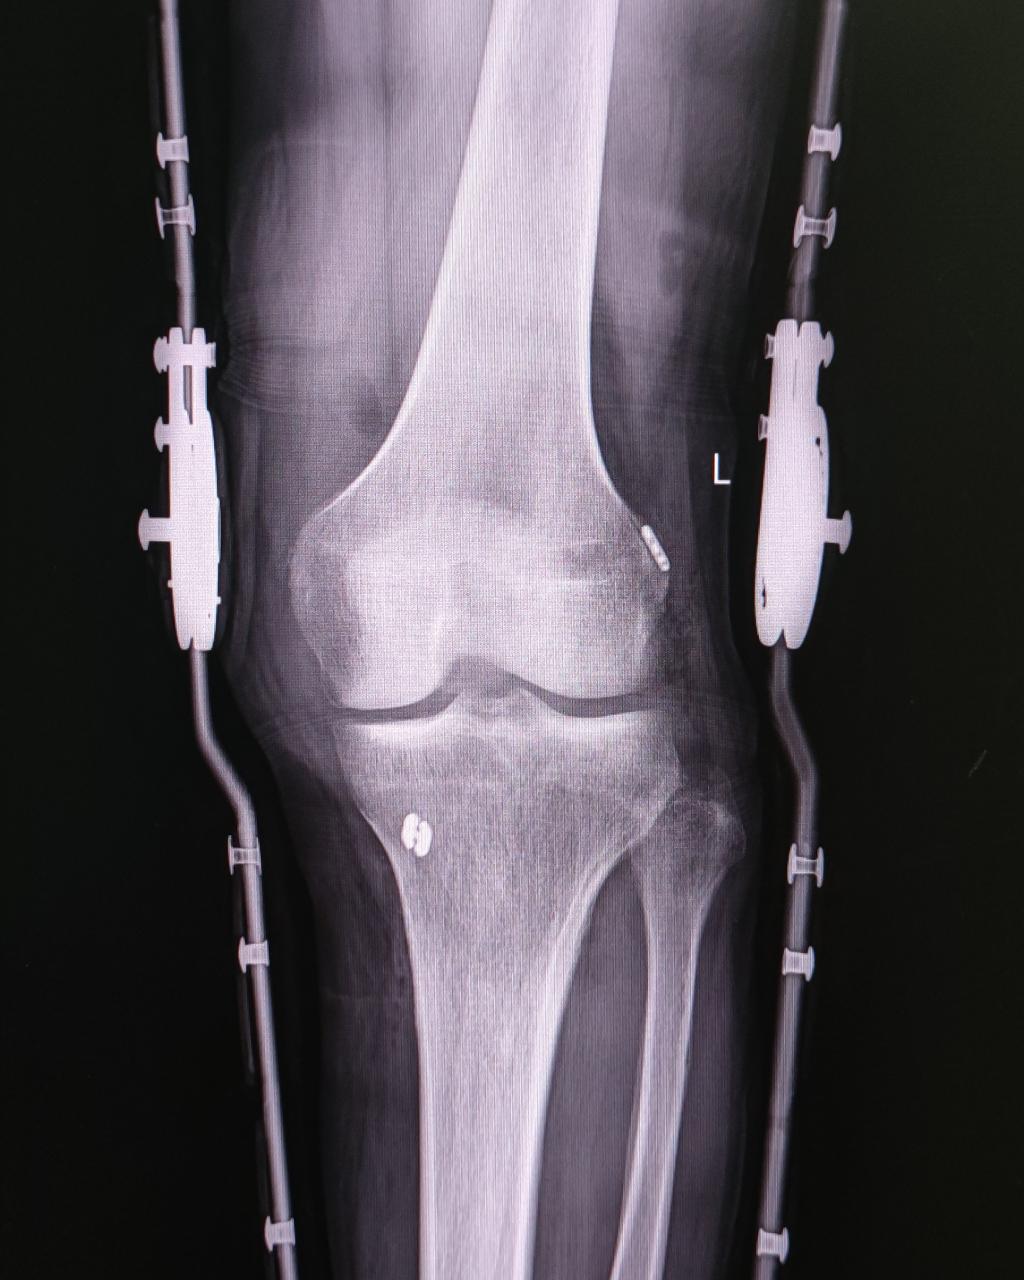

术后复查X线